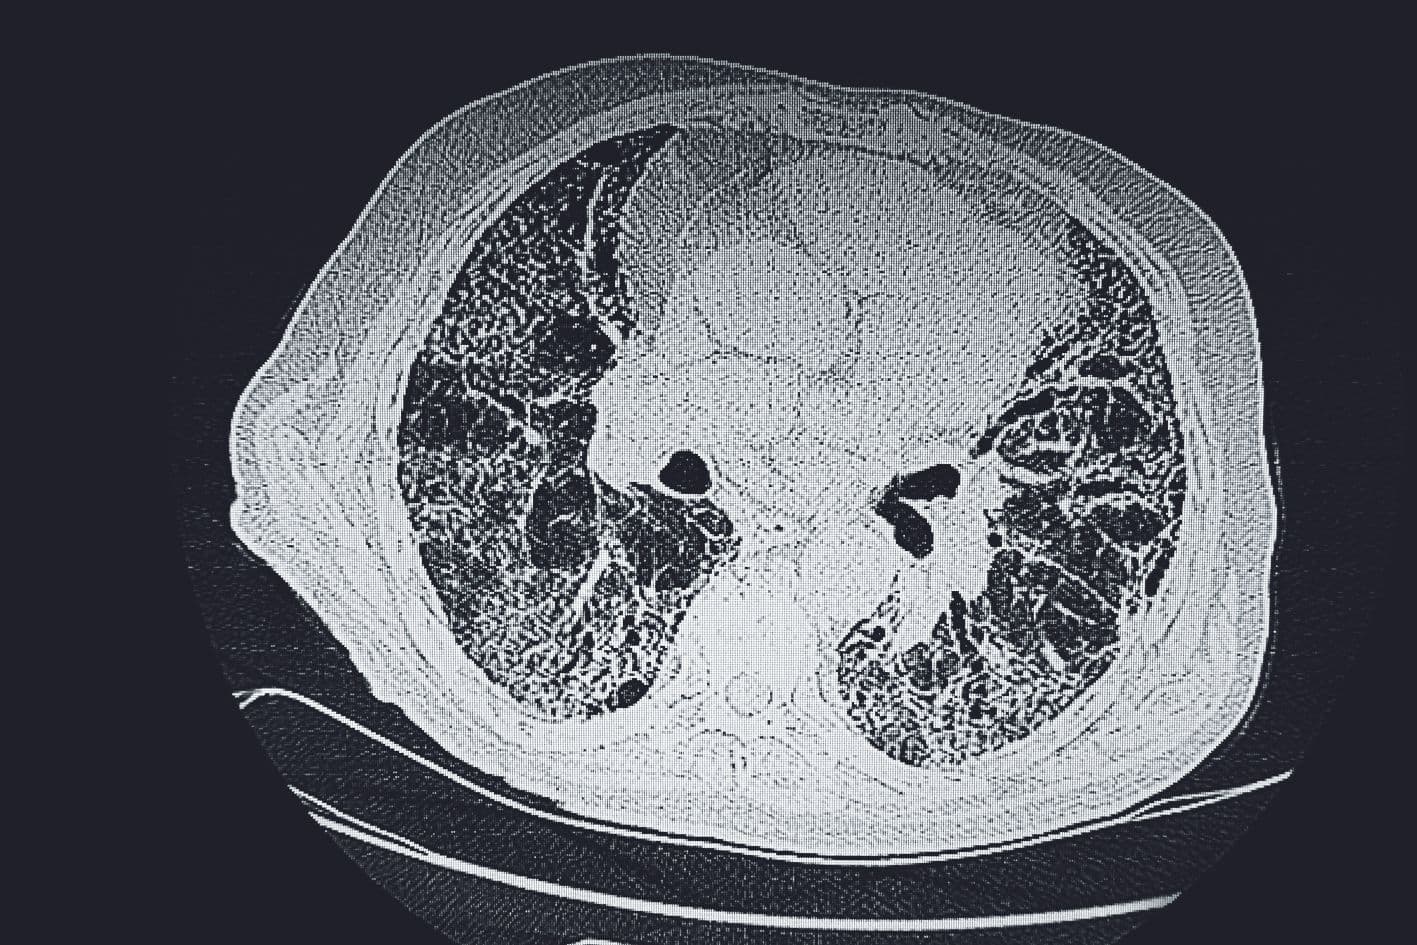

Au cours du vieillissement normal, des cellules sénescentes 1 s’accumulent dans l’organisme : elles ne se divisent plus, secrètent des molécules inflammatoires, altèrent leur environnement et participent au développement des maladies chroniques liées à l’âge, comme l’ostéoporose, la fibrose 2 pulmonaire ou hépatique et même certains cancers. Normalement, ces cellules vieillissantes sont éliminées par le système immunitaire, et plus particulièrement par les cellules dites tueuses naturelles, ou cellules NK. Une étude dirigée par Julien Cherfils-Vicini, de l’Institute for Research on Cancer and Aging de Nice (IRCAN), vient de découvrir un mécanisme par lequel certaines d’entre elles échappent à cette élimination : elles produisent une molécule appelée ganglioside GD3 qui agit comme un bouclier à leur surface et les rend en quelque sorte invisibles aux cellules immunitaires de type NK.

Chez des souris modèles, les chercheurs ont alors essayé de lever ce blocage immunitaire et de restaurer cette reconnaissance par les cellules NK grâce à une immunothérapie 3. Ils ont en effet développé des anticorps anti-GD3 qu’ils ont administrés aux rongeurs. Résultats : les cellules immunitaires de type NK ont pu effectuer le travail correctement et éliminer les cellules vieillissantes. Les chercheurs ont alors constaté une réduction marquée des dommages liés au vieillissement chez les animaux, et plus particulièrement une atténuation de la fibrose pulmonaire et hépatique ainsi qu’une amélioration des processus de remodelage osseux.